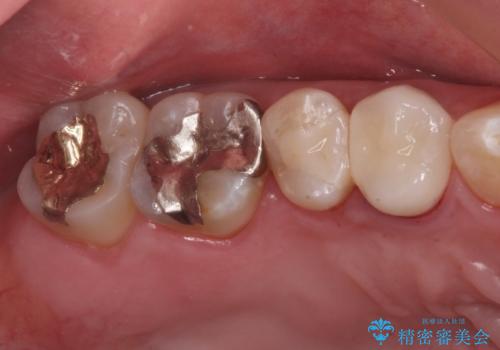

拡大鏡下で虫歯を全て除去しゴールドインレーにて治療しました。

- ゴールドインレー 7.7万円費用は治療当時の料金となります

ゴールドインレーはメタルインレーに比べて、歯と詰め物の隙間が生じにくため

虫歯菌が侵入することなく、虫歯の再発のリスクが低いです。